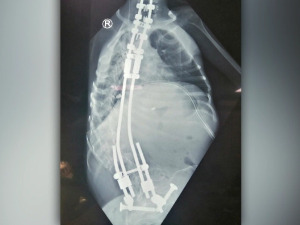

Сарадња са професором Вентуром донела је спас бројним пацијентима са најтежим деформитетима кичме

У протекле четири године, чувени шпански хирург професор Норберто Вентура са својим тимом, али и са нашим стручњацима, урадио је 112 хируршких захвата, чак 70 операција код деце са најтежим деформитетима...